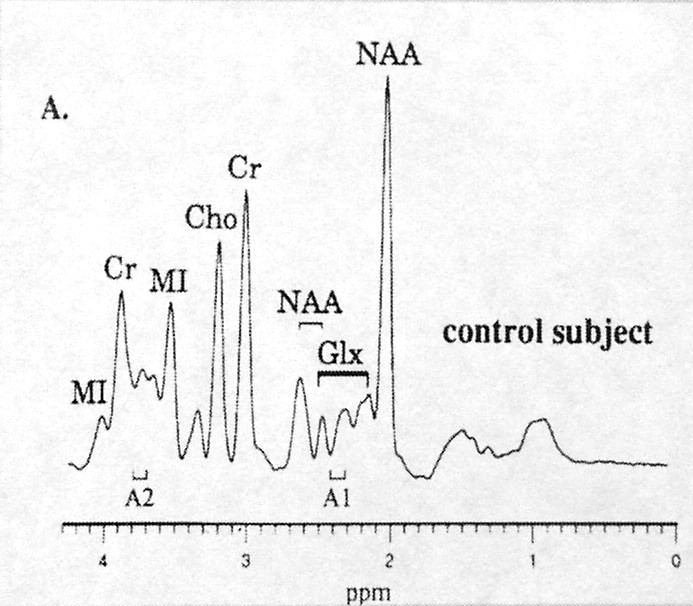

Utilizada com maior frequência no passado, a técnica de espectrospia com voxel único (SV), tem sido usada atualmente como ferramenta adicional na investigação de estados demenciais, colhendo amostras de voxel colocado em diferentes partes do sistema nervoso mais vulneráveis ao processo degenerativo, em especial no cíngulo posterior (doença de Alzheimer), utilizando tempo de echo curto (30ms), para avaliar comportamento do aminoácido Mio-inositol (um aminoácido considerado marcador glial – Mio) e sua relação com a creatina (Mio/Cr) e com o N-Acetil Aspartato (NAA/Mio).

Na espectroscopia de voxel único (SVS ou EVU), o sinal de RM é maior e tem traçado com informações de metabólitos mais precisas, utilizando tempos de echo de 30 e de 144ms. A técnica de voxel único continua importante no diagnóstico de lesões cerebrais com efeito de massa (tumores, processos inflamatórios), porém mais usada para lesões homogêneas e bem delimitadas